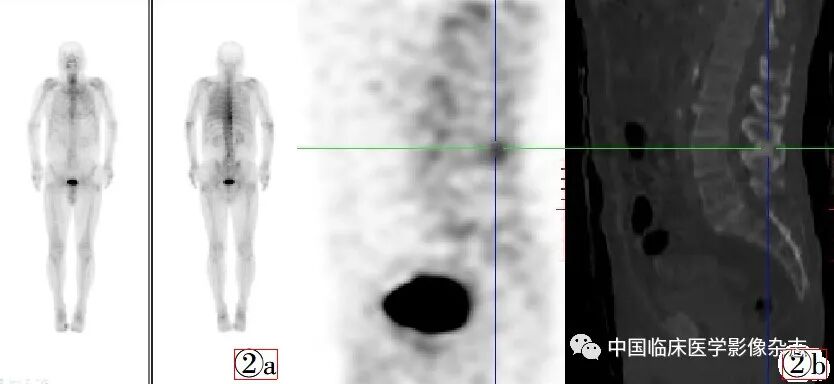

例2:男,76岁,确诊左肺上叶小细胞肺癌1周,未治疗,左侧肩背疼1月余,无外伤史,为了解有无骨转移行全身骨显像检查。扫描方法同例1。全身骨显像(图2)显示L4棘突放射性分布增高,断层CT定位于L3~L4椎体棘突间,可见相邻两棘突骨质增生硬化。临床诊断为Baastrup病。

图2  男,76岁,确诊左肺上叶小细胞肺癌1周。图2a:全身骨显像显示L4棘突放射性分布增高。图2b:断层CT定位于L3~L4椎体棘突间,可见相邻两棘突骨质增生硬化(左侧第10后肋及胸椎中下段右侧放射性分布增高灶证实为良性病变)。